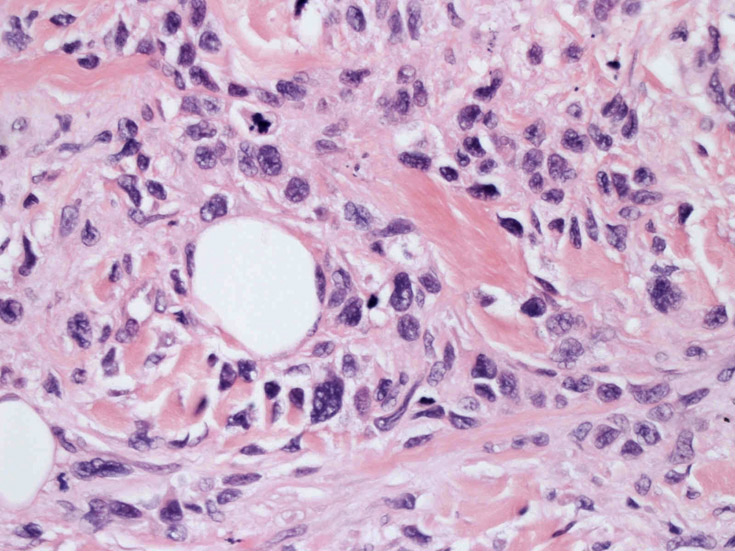

皮膚生検組織。細胞浸潤が表皮, 表皮真皮境界部, 真皮, 皮下組織にびまん性に認められる。血管中心性に結節様の分布があるように見える。

皮膚に異型細胞の浸潤がみられる。異型細胞は表皮内に浸潤するほか、表皮真皮境界部, 真皮, 皮下脂肪組織にもびまん, 結節様の浸潤所見を示す。血管周囲に浸潤、集蔟する所見も多く見られる。 増殖浸潤細胞の核には類円形や腎臓形, またはへこみ, 切れ込み, 溝などを有する多型な核が認められる。クロマチンは粗でvesicularな核が多い。核小体の明らかな核もある。好エオジン性の核内封入体様構造も少数に見られた。mitosisは容易に認められる。hyperchromaticな多型核, bizzarreな細胞が高頻度に認められ異型度は高いと考えられる。細胞質は境界不明瞭, 淡明または泡沫様の 好エオジン性胞体である。

免疫染色 浸潤細胞はCD1a+, S100+, Langerin+, HLA-DR+, CD4+, CD45+, CD68+. MIB-1 index:24.4%